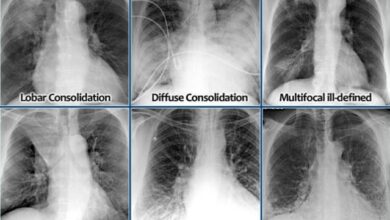

Interpreting X-Ray & CT Scan Results For Injuries and Illness with Mubadala Health

X-rays and computed tomography (CT) scans are valuable diagnostic imaging tools used to evaluate injuries, illnesses, and abnormalities in the…